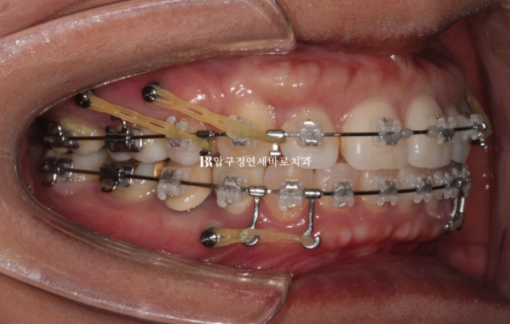

We decided to treat with Clippy-C, and after placing a total of six mini-screws, four in the upper jaw and two in the lower jaw, treatment was carried out.

Below, the entire dentition is being pushed backward, and the upper dentition is being pushed backward while also being moved upward.

22.09~24.04